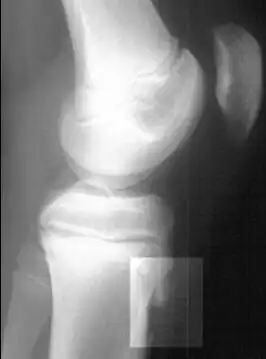

Radiografia lateral do joelho demonstrando fragmentação da tuberosidade da tíbia, com o tecido superabundante.

Os fatores de risco incluem o uso excessivo, especialmente esportes que envolvem correr ou pular. O mecanismo subjacente é a tensão repetida na placa de crescimento da tíbia superior. O diagnóstico é tipicamente baseado nos sintomas. Uma radiografia simples pode ser normal ou mostrar fragmentação na área de fixação.[5]

O diagnóstico é feito com base em sinais e sintomas,[9][15] palpação da tuberosidade da tíbia gerando dor,[16] além do exame radiográfico.[17]